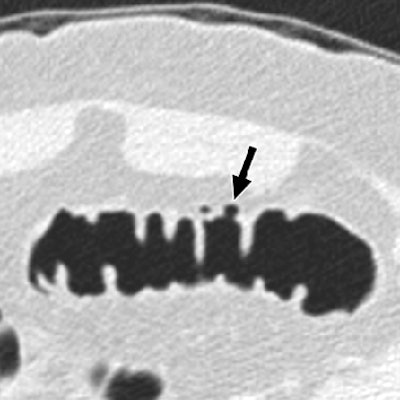

| Correlation of 3D endoluminal virtual dissection display with traditional images at CT colonography in the sigmoid colon of a 70-year-old man (above). Typical 3D endoluminal virtual dissection display of a 15-cm colonic segment. Diverticulum (arrow) and prominent fold (arrowhead) are correlated with 2D multiplanar and perspective, volume-rendered images for diagnosis. Below, 2D transverse image shows diverticulum (arrow) also seen above. Images republished with permission of the American Roentgen Ray Society © from AJR 2007; 189: 672-680 by C. Daniel Johnson, Joel G. Fletcher, Robert L. MacCarty, Jay N. Mandrekar, William S. Harmsen, Paul J. Limburg, and Lynn A. Wilson. |

![]() |